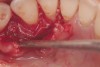

Subgingival calculus and severe bone loss.

Figure 18

The patient had been referred for an implant consultation for the mandibular right canine. She had very deep probing depths on the lingual. When the flap was raised, a significant amount of subgingival calculus was seen as a local risk factor (Figure 18). However, she had no significant pathology to remove from the situation. Debridement was performed the same as in Case 3 with the rotary ultrasonic and manual instrumentation.